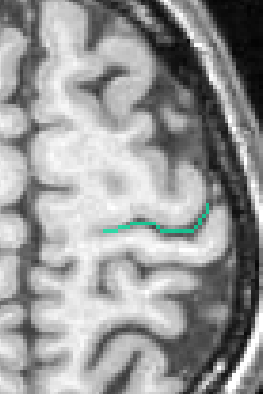

Each fold includes several buckets of voxels corresponding to the topologically simple surface making up its core (GREEN), its bottom lines (including branche's bottoms) (RED) and a few additional voxels corresponding to small or spurious branches (CYAN). Here is the example of a central sulcus:

If you want to get only one sulcus, or a small list of sulci, write their label in the attibute "label_values". For instance "S.C._left" or "S.C._left S.F.sup._left":